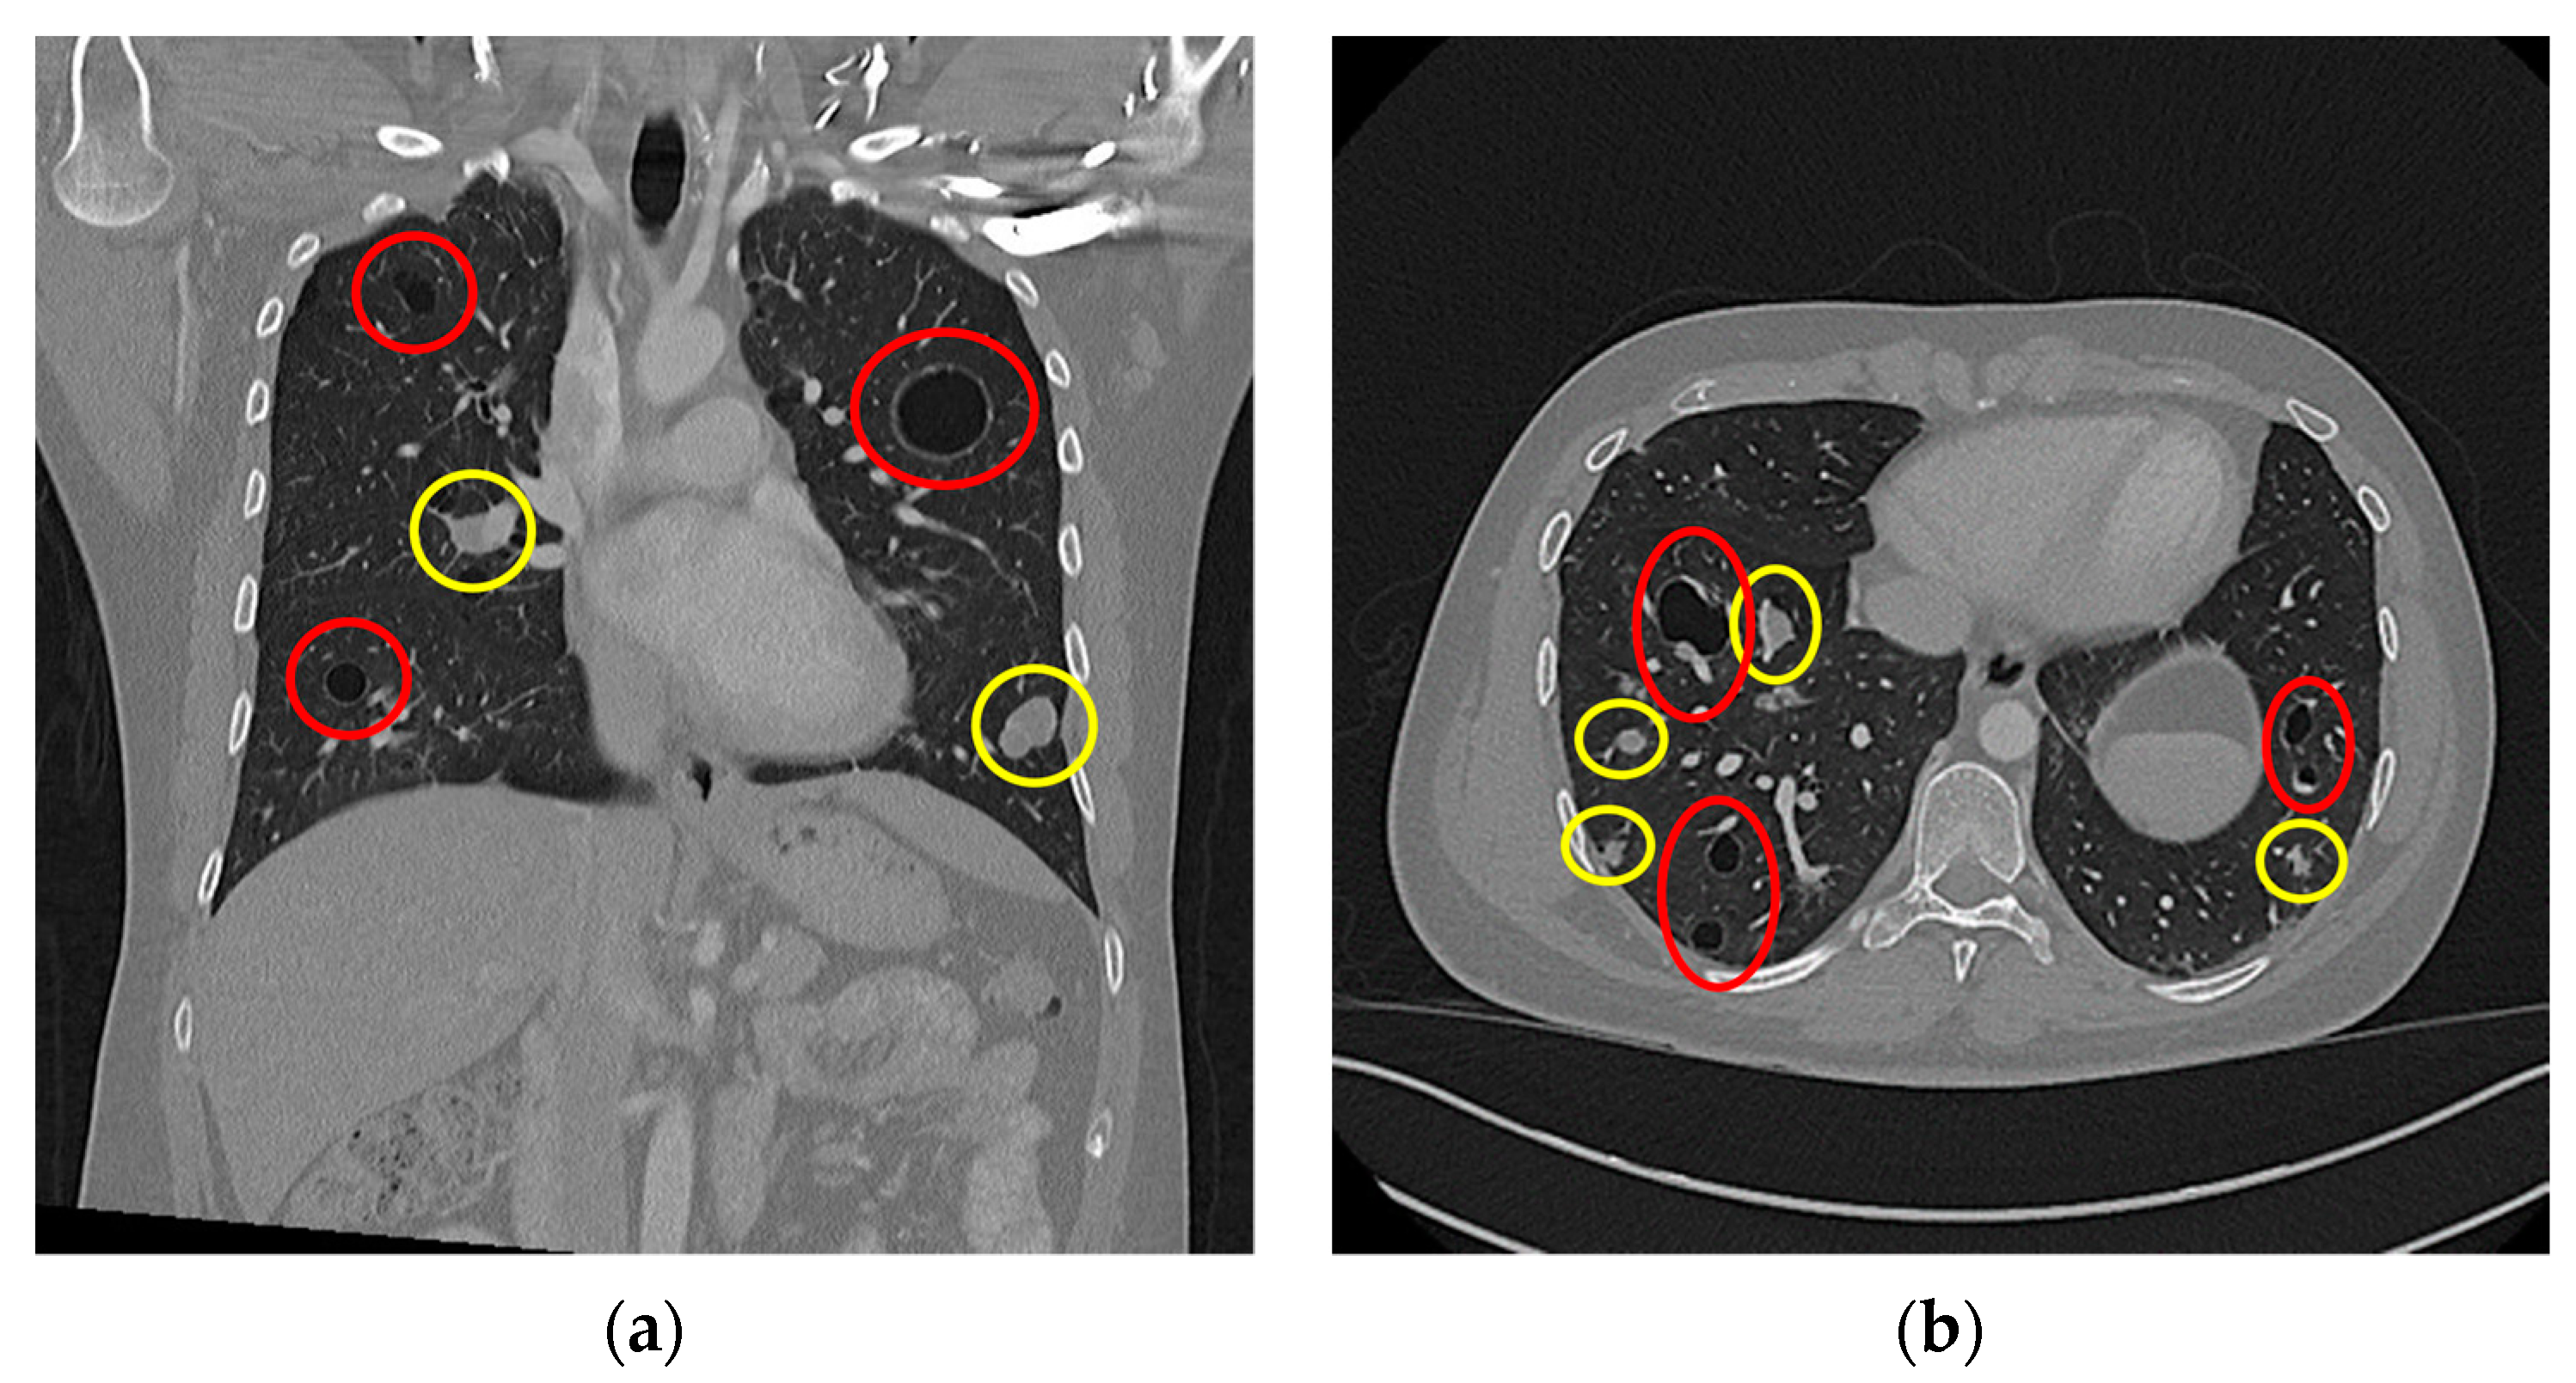

As a subsidiary finding of the initial nuchal CT scan, multiple dense soft-tissue structures were observed in the apical pulmonary tissue of both lung sides. This raised concerns for possible malignancy as well as the presence of metastatic disease. In line with standardised follow-up staging protocols, as confirmed by a multidisciplinary board conference, a staging CT scan of the thorax and abdomen was conducted. In this scan, a multitude of pulmonary masses were documented: we saw bilobar masses of both hyperdense solid (n > 30) and hypodense cystic (n > 40) consistencies. These masses are shown in Figure 3, with the solid masses circled by a yellow border and the cystic masses circled by a red border. Some of the solid masses were septally divided, and several solid masses were directly adherent to the cystic lesions. The largest solid lesion in the left lower pulmonary lobe measured approximately 21 mm (Figure 3a), whereas the largest cystic lesion, located in the left upper pulmonary lobe, measured approximately 35 mm (Figure 3b).

Our patient’s case is unique as in that this is the first recorded case of an aneurysmal fibrous histiocytoma’s primary pulmonary metastasis when compared to thes cientific literature. In all other recorded cases (n = 7), the first sites of metastatic dissemination were locoregional lymph nodes [6,8,12,13,14]. However, our case also shares many similarities with the existing literature. Doyle et al. reported a singular cystic pulmonary metastasis measuring 50 mm in diameter, whereas our patient’s largest cystic pulmonary metastasis measured 35 mm in diameter (Figure 3a). A histopathological examination of our patient’s pulmonary metastases reported that they were morphologically similar to the primary nuchal tumour, with large, haemosiderin-laden and blood-filled spaces as well as CD68-positive fibroblastic cells and sparse mitotic activity. This matched Doyle et al.’s and Wood et al.’s histopathological and immunohistochemical results [6,8].

Figure 3. Thoracal CT scan: (a) coronar projection; (b) axial projection. Both images show multiple cystic (highlighted in red) and solid (highlighted in yellow) lesions.